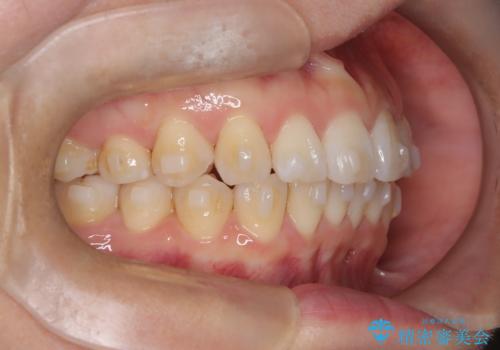

- 「歯のガタつきが気になる」「前歯の真ん中がずれている」との主訴で来院されました。診察の結果、上下の歯列に中等度の叢生(凸凹)があり、特に前歯の位置のずれ(正中の偏位)が目立つ状態でした。見た目だけでなく、かみ合わせにも影響を与える可能性があるため、全体的なバランスの改善が必要と診断しました。

治療はインビザラインを使用し、1~2週間ごとに新しいマウスピースに交換しながら段階的に歯を移動させていきました。特に上下の正中が揃うよう、奥歯や前歯の位置関係に注意を払いながら細かく設計を調整。途中の確認でも、左右のバランスが取れてきたことをご本人も実感されていました。

治療期間は約1年半で、ガタついていた歯列はきれいに整い、上下の前歯の真ん中もぴったりと揃えることができました。透明なマウスピースのため周囲に気づかれず治療が進み、快適に続けられたとの感想もいただいています。